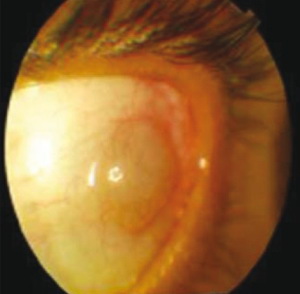

| Фото. Цистицеркоз глаз: А Киста цистицерка под конъюнктивой в наружном углу глаза; Б цистицерк на глазном дне, вертикальная стрелка указывает место выхода паразита через сосуды сетчатки поврежден пигментный эпителий сетчатки, горизонтальная стрелка указывает на отслойку сетчатки вокруг цистицерка, белое пятно в центре кисты это сколекс паразита; В На УЗИ цистицерк на глазном дне киста (толстая стрелка) и сколекс (тонкая стрелка) паразита. | ||